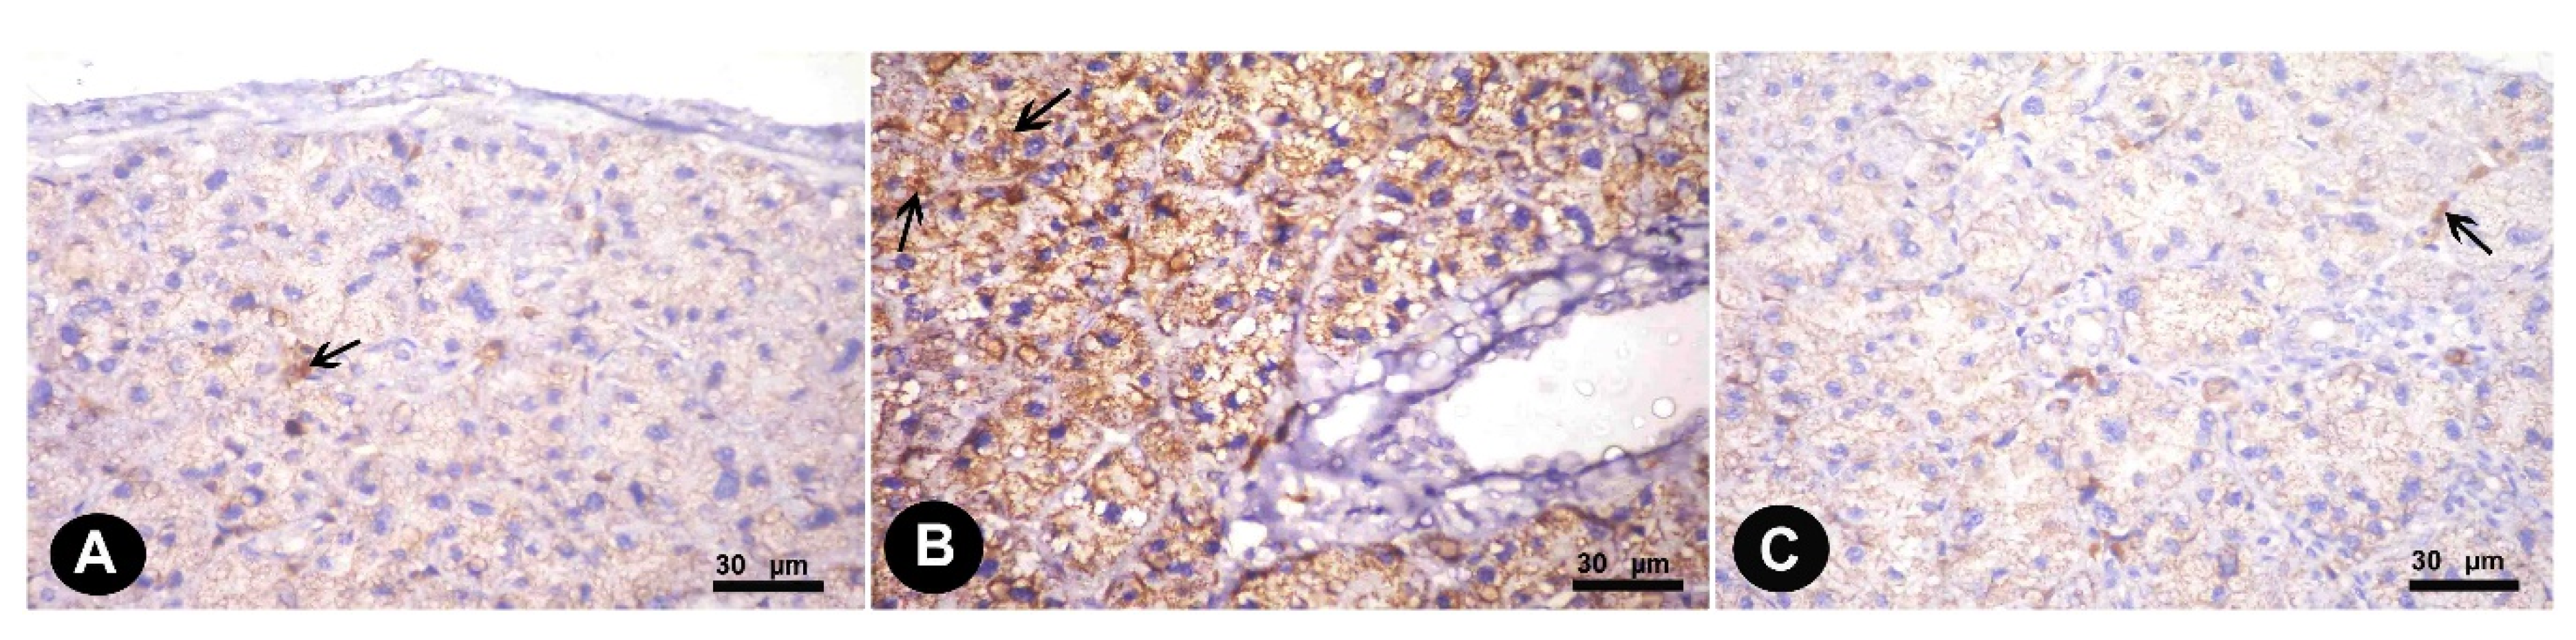

3.1.2. Immunohistochemical Results

3.1. Histopathological Results

3. Results